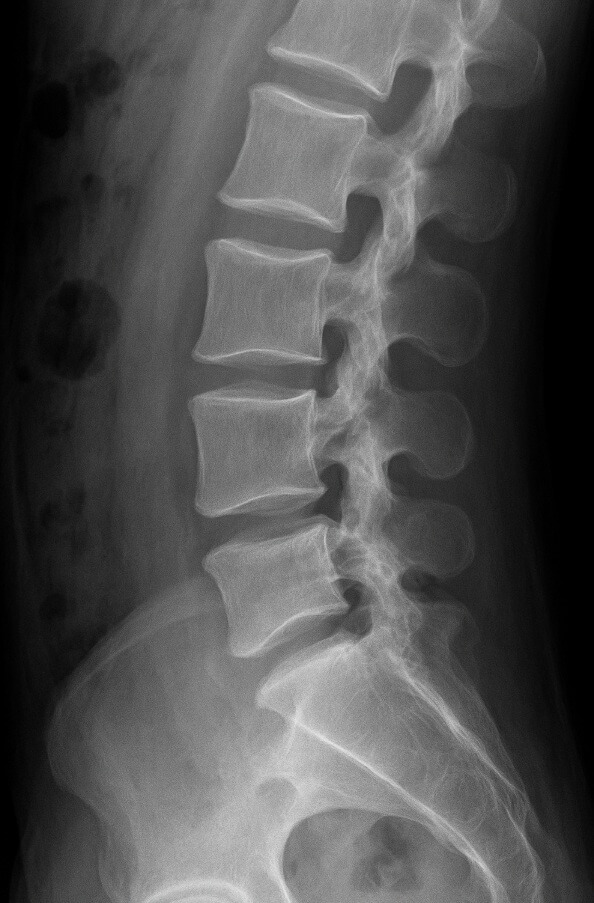

척추관 협착증은 신경이 눌리는 ‘신경근성 간헐적 파행’ 증상 때문에 허리를 굽혔을 때 통증이 줄어드는 특징이 있습니다. 따라서 허리를 ‘앞으로 굽히는(flexion)’ 스트레칭이 통증 경감에 효과적입니다.

척추과 협착증 운동법 아래 그림을 보면서 따라해 보세요!!!!!!!

2. 척추관 협착증 허리 강화 운동

스트레칭으로 신경 공간을 확보했다면, 이제 주변 근육을 단단히 받쳐 줄 차례입니다. 허리(요추)와 엉덩이(둔근)를 강화하면 척추에 가해지는 압력을 분산시켜 협착증 진행 속도를 늦출 수 있습니다. 중요한 것은 ‘허리를 뒤로 꺾는 연속 동작’을 피하고, 중립 또는 살짝 굽힌 상태에서 힘을 키우는 것입니다.